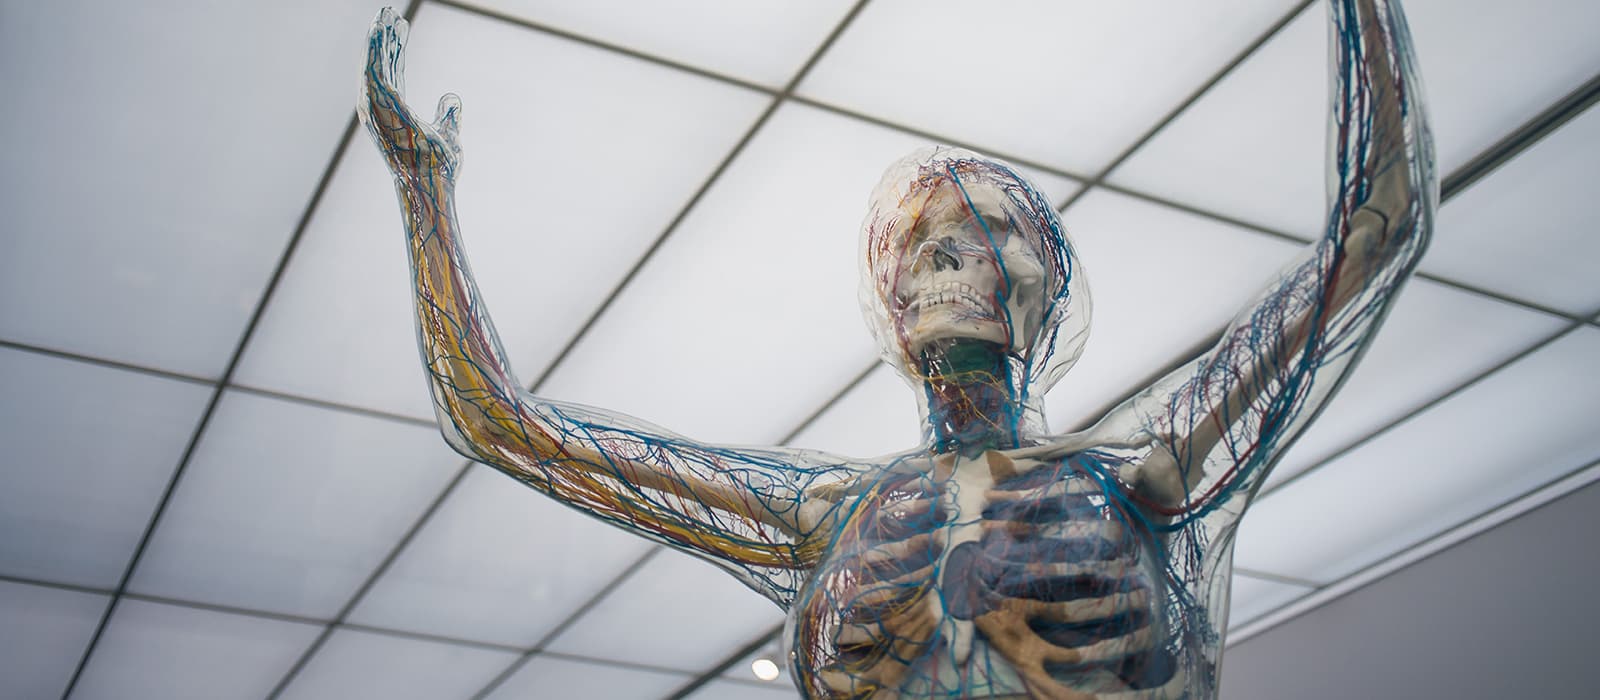

Clinica s-a înființat din dorința de a oferi cele mai bune servicii într-un cadru cât mai plăcut și cu beneficiul aparaturilor de specialitatea care să ofere cele mai corecte diagnostice.

Avem o echipă multidisciplinară poate oferi o succesiune de etape pentru o diagnosticare cât mai complexă.

Viziunea noastră este să devenim prima alegere și un standard în tot ceea ce înseamnă calitatea excepțională a îngrijirii medicale, relația caldă, plină de atenție și compasiune față de pacienți, și să fim cunoscuți pentru serviciile medicale de cea mai înaltă competență, bazată pe un corp medical de excepție, pe inovație, tehnică și tehnologie medicală de vârf.

Clinica Dr. Stoica oferă specialitățile de medicină internă, obstetrică-ginecologie, urologie, neurologie și psihiatrie, acceptând și consultații prin Casa de Sănătate.

Consultări și interpretări analize, electrocardiogramă, ecografii, Ecografie Doppler, EKG, Monitorizare holter